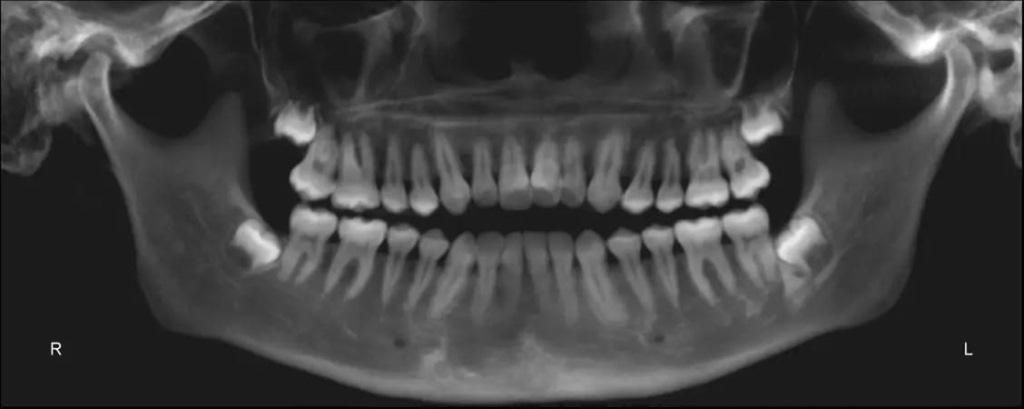

У нее было симметричное лицо, недостаточная видимость резцов в покое и повышенная видимость десен в задних сегментах во время улыбки. Отмечалась гипертрофия жевательных мышц (фото 35). Были отмечены нормальные мезио-дистальные соотношения зубных дуг, а также молярные и клыковые взаимоотношения Class I. Средние линии зубов были выровнены по центру. Однако наблюдалась тенденция к переднему открытому прикусу, отсутствию как избыточного, так и отрицательного крутящего момента на резцах верхней челюсти. Кроме того, у пациентки наблюдались признаки износа зубов и искривления резцов нижней челюсти - оба эти явления часто встречаются у пациентов с бруксизмом или привычкой сжимать зубы (фото 36).

Фото 36a-e: Дооперационные экстраоральные фотографии.

Панорамная рентгенограмма выявила отсутствие третьих моляров, хорошую морфологию корней и параллельность резцов (фото 37). Цефалометрическая рентгенограмма и трассировка показали тенденцию к формированию скелета III класса, характеризующегося коротким основанием черепа и длинной нижней челюстью - чрезмерным развитием нижней трети лица. Наклон верхних резцов внутрь, к нёбу (ретроклинация), и проклинированные (проклонённые) нижние резцы (фото 38).